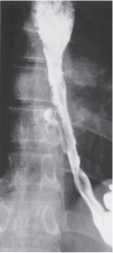

Conservative management [of esophageal perforation] should not be used in patients who have free perforations into the pleural space. Cameron proposed three criteria for the non-operative management of esophageal perforation: (a) The barium swallow must show the perforation to be contained within the mediastinum and drain well back into the esophagus (Fig. 25-3), (b) symptoms should be mild, and (c) there should be minimal evidence of clinical sepsis. If these conditions are met, it is reasonable to treat the patient with hyperalimentation, antibiotics, and cimetidine to decrease acid secretion and diminish pepsin activity. Oral intake is resumed in 7 to 14 days, dependent on subsequent radiographic examinations. (See Schwartz 9th ed., p 876.)

FIG. 25-3. Barium esophagogram showing a stricture and a contained perforation following dilation. The injury meets Cameron criteria: It is contained within the mediastinum and drawn back into the esophagus, the patient had mild symptoms, and there was no evidence of clinical sepsis. Nonoperative management was successful.